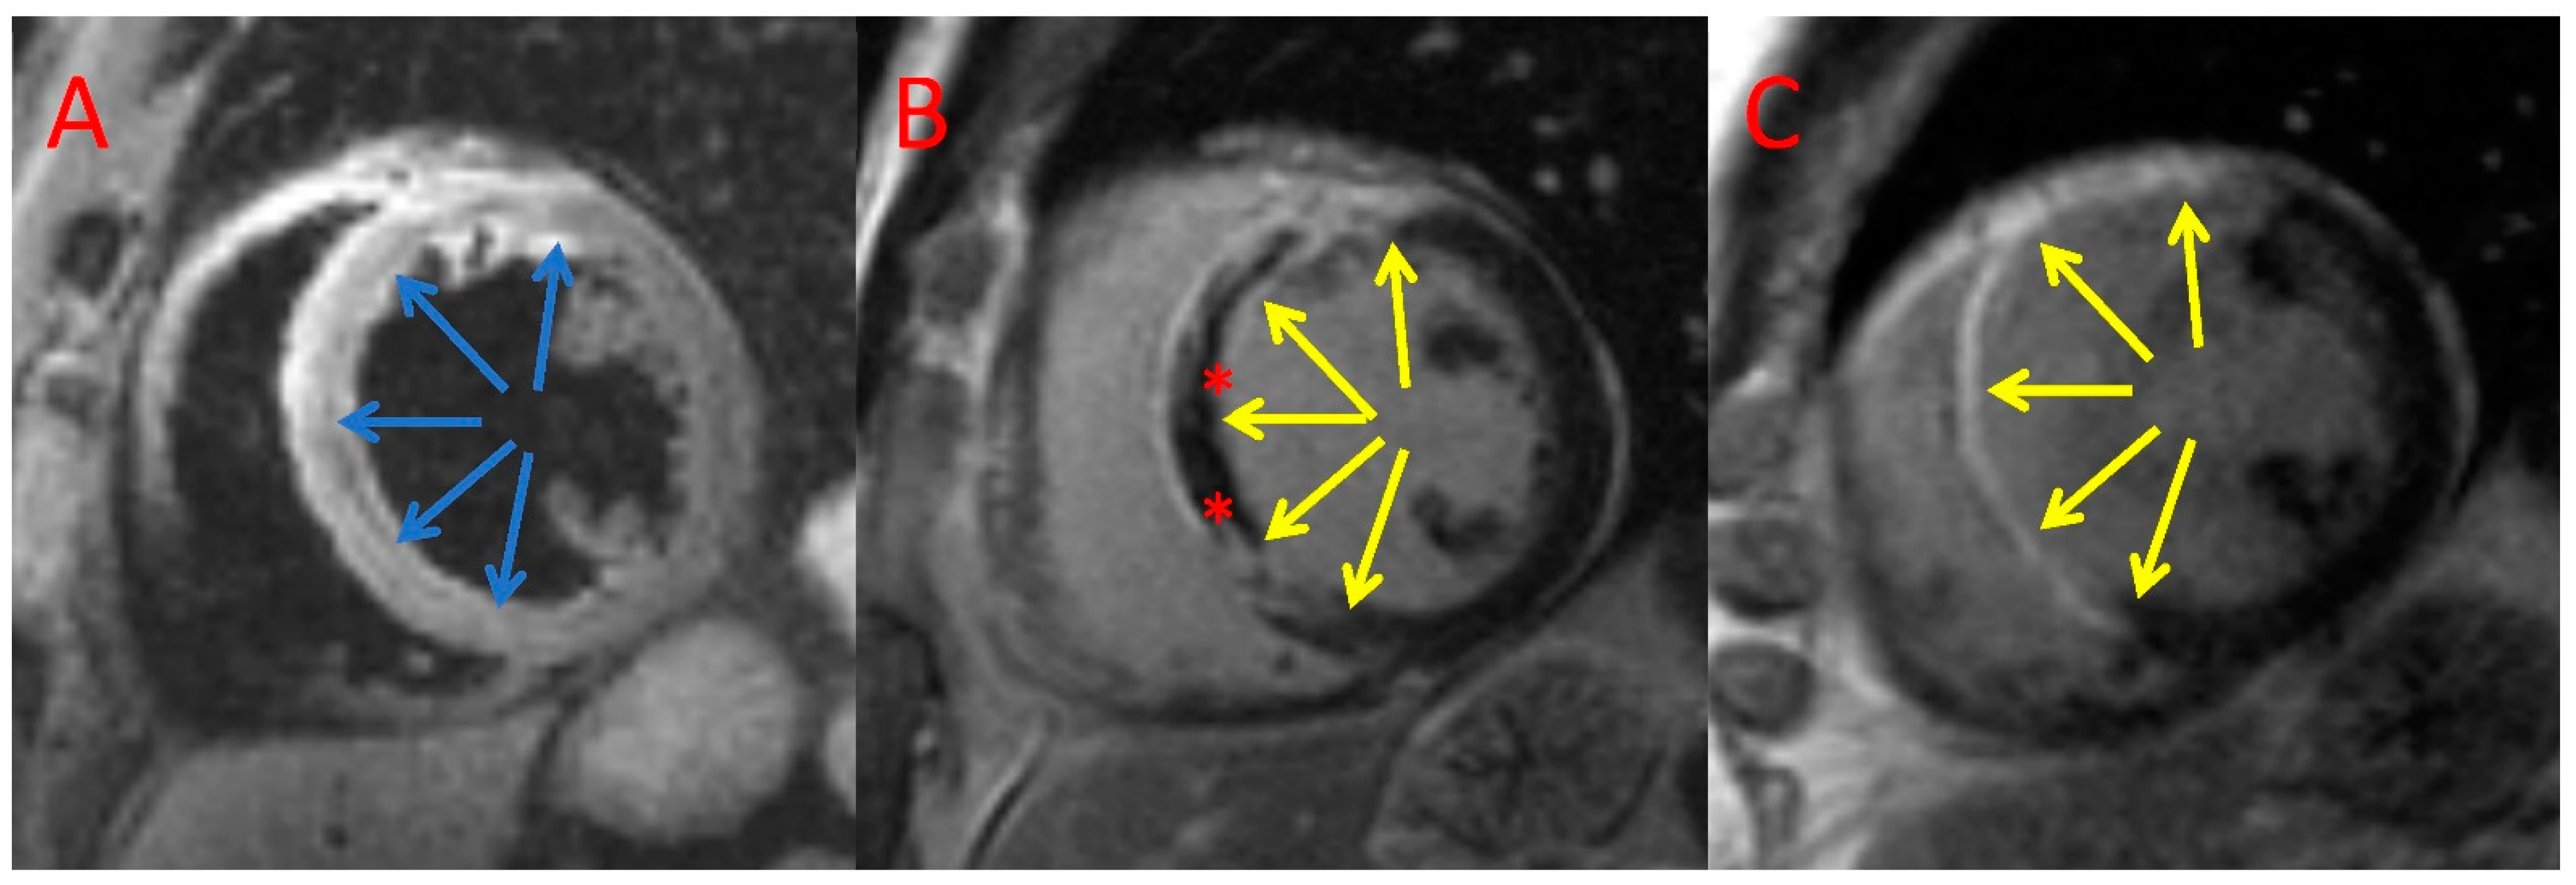

2.6. CMR Analysis

3.4. CMR Assessment